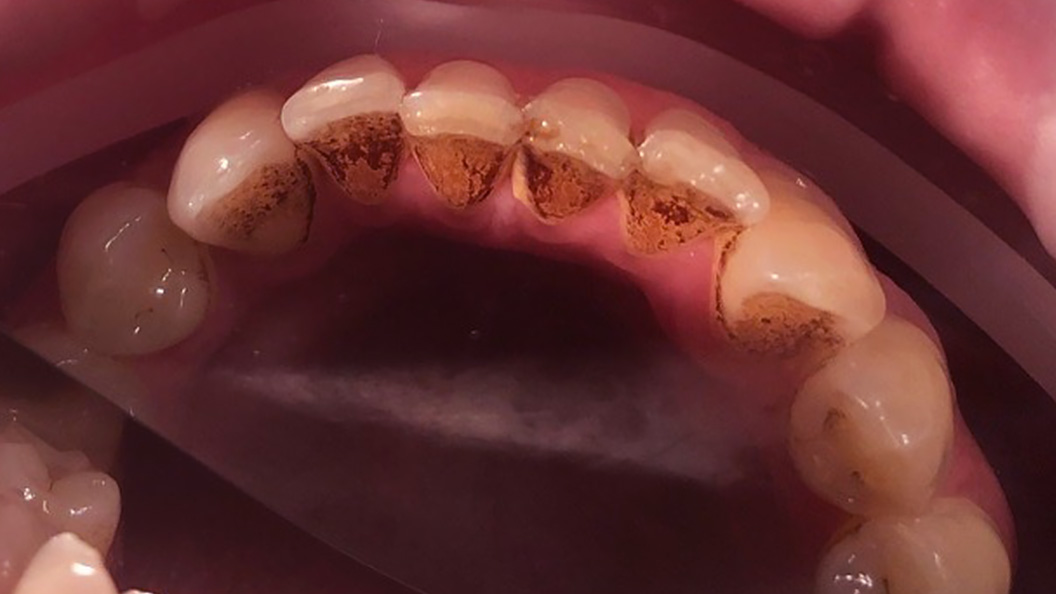

До и после лечения

Пациент обратился с жалобой на наличие зубных отложений и кровоточивость во время чистки зубов. Во время осмотра были выявлена над- и поддесневые отложения. Маргинальная десна отечна и гипермирована, при зондировании кровоточит.

Ход лечения:

- удаление над- и поддесневых отложений с помощью УЗ-аппарата

- профессиональная чистка зубов пастой Detarine Z